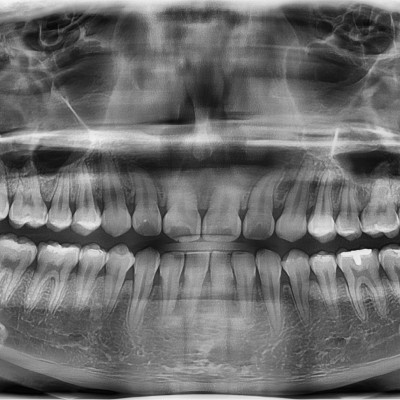

#18,28,38,48 사랑니 발치 #18,28,38,48 사랑니 발치 구강 외과 전문의가 당일 발치했습니다. --------------------..